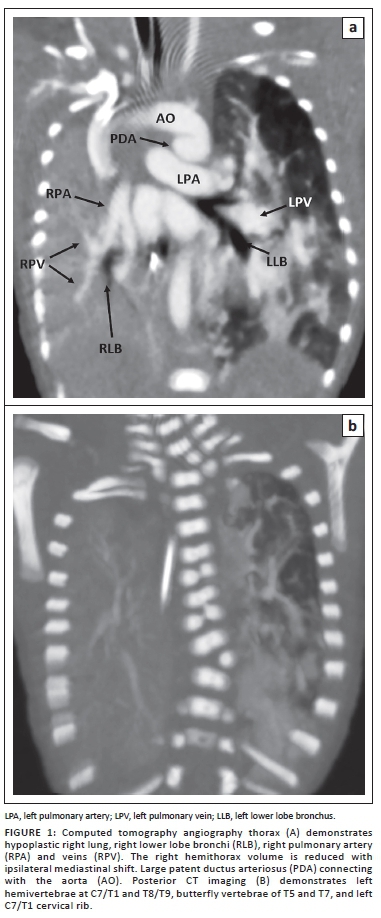

Serial chest radiographs (CXR) showed persistent right homogeneous opacity. Echocardiography demonstrated a patent foramen ovale (PFO), a large patent ductus arteriosus (PDA) and mild tricuspid regurgitation. Computed tomography angiography (CTA) of the thorax (Figure 1) revealed a small right hemithorax volume with a hypoplastic right pulmonary artery (RPA) and vein as well as the right segmental bronchi consistent with pulmonary hypoplasia. PFO and a large PDA were present. At thoracic spine radiography, there was levoscoliosis with lateral left hemivertebrae at C7/T1 and T8/T9, butterfly vertebrae of T5 and T7, and a left C7/T1 cervical rib (Figure 1).